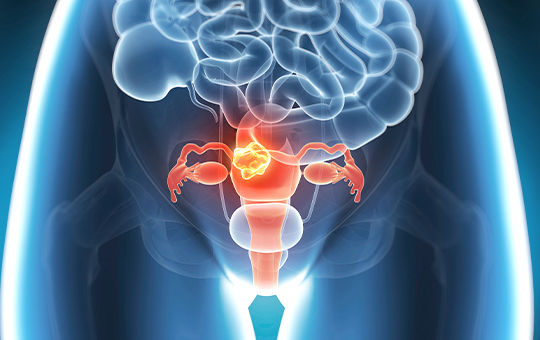

5대암 검진은 암을 조기에 발견해

생존율을 높이기 위한 국가 지원 검진입니다.

대한민국 국민들이 가장 많이 걸리는5대 암에 대한 검진입니다.

우리나라 국민의 사망원인 1위인 암은 자각하는 증상이 거의 없어

조기 진단과 예방이 가장 중요합니다.

공단 90% / 수검자 10% 부담 (단, 자궁경부암은 전액 공단 부담)